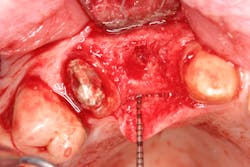

- Suture technique: lack of tension-free closure (figures 1 and 2), incision design doesn’t include keratinized tissue, failure to approximate tissue flaps (use of horizontal/vertical mattress helps)

- Surgical technique: failure to stabilize graft/membrane, lack of implant/cover-screw stability, insufficient amount of flap tissue in suture bite